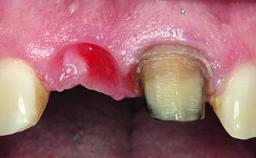

A 32-year-old female Caucasian patient with a compromised maxillary right central incisor was referred to us by a general dentist. Her chief complaints were discomfort and mobility of tooth 11 with unsatisfactory esthetics due to discoloration. The patient reported a previous trauma, some years earlier, as the origin of pathology on the afflicted tooth. Anamnesis was negative for any other dental or periodontal pathology in the remaining dentition. The patient did not take any medication and reported to be a light smoker (5–10 cigs/day). She had high esthetic expectations of her treatment. The extraoral examination revealed a high smile line with full exposure of her maxillary teeth and surrounding soft tissue in the area between the second premolars.

Replacement of an Upper Right Central Incisor with Root Resorption: Ridge Preservation, Delayed Placement of an NC Bone Level Roxolid Implant